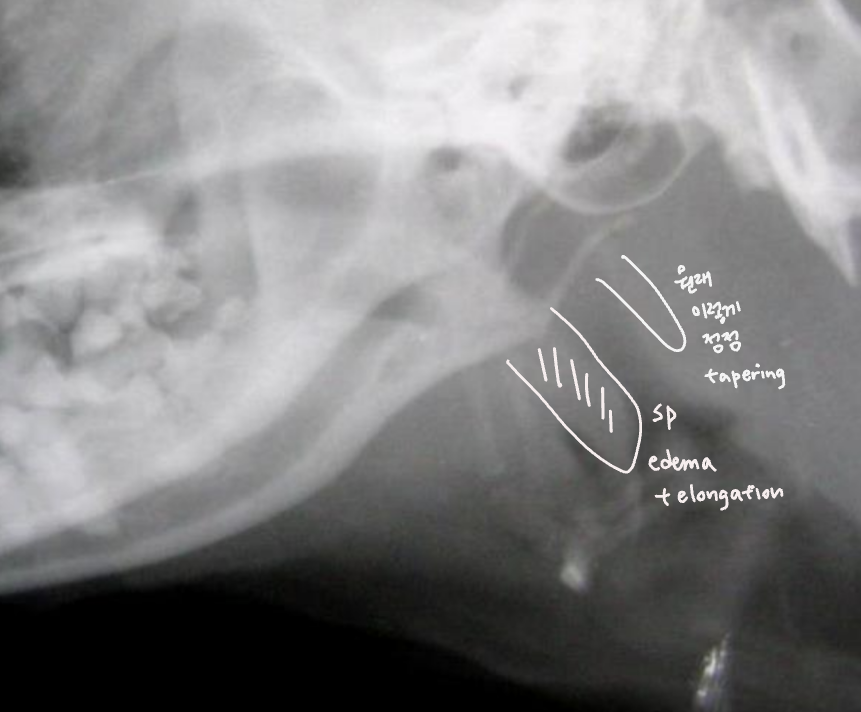

- English bulldog, Pug, Pekingese, French Bulldog, Bonston Terrier.. ์์ธ - Skull์ base๊ฐ ์ ์ ์ ์ผ๋ก ์งง์ - ๊ตฌ์กฐ์ ์ผ๋ก ์ผ๊ตด์ด ์งง์ ๊ตฌ์กฐ๊ฐ ๊ณผ๋ฐ๋จ Complex - stenotic nares (๋น๊ณตํ์ฐฉ) - soft palate edema & elongation (์ฐ๊ตฌ๊ฐ๋ ธ์ฅ) - laryngeal edema, saccules, collapase, paralysis - (dynamic) pharyngeal collapse GI complication - Hiatal hernia - gastroesophageal reflux (์ญ๋ฅ์ฑ ์๋์ผ) |

| Pharyngeal collapse : ํธ๊ธฐ ๋ ์ข์์ง - ์ฆ์์ ํก๊ธฐ์์ ๋ ์ฌํจ (ํก๊ธฐ์ฑ ํธํก๊ณค๋) ![]() ![]() |